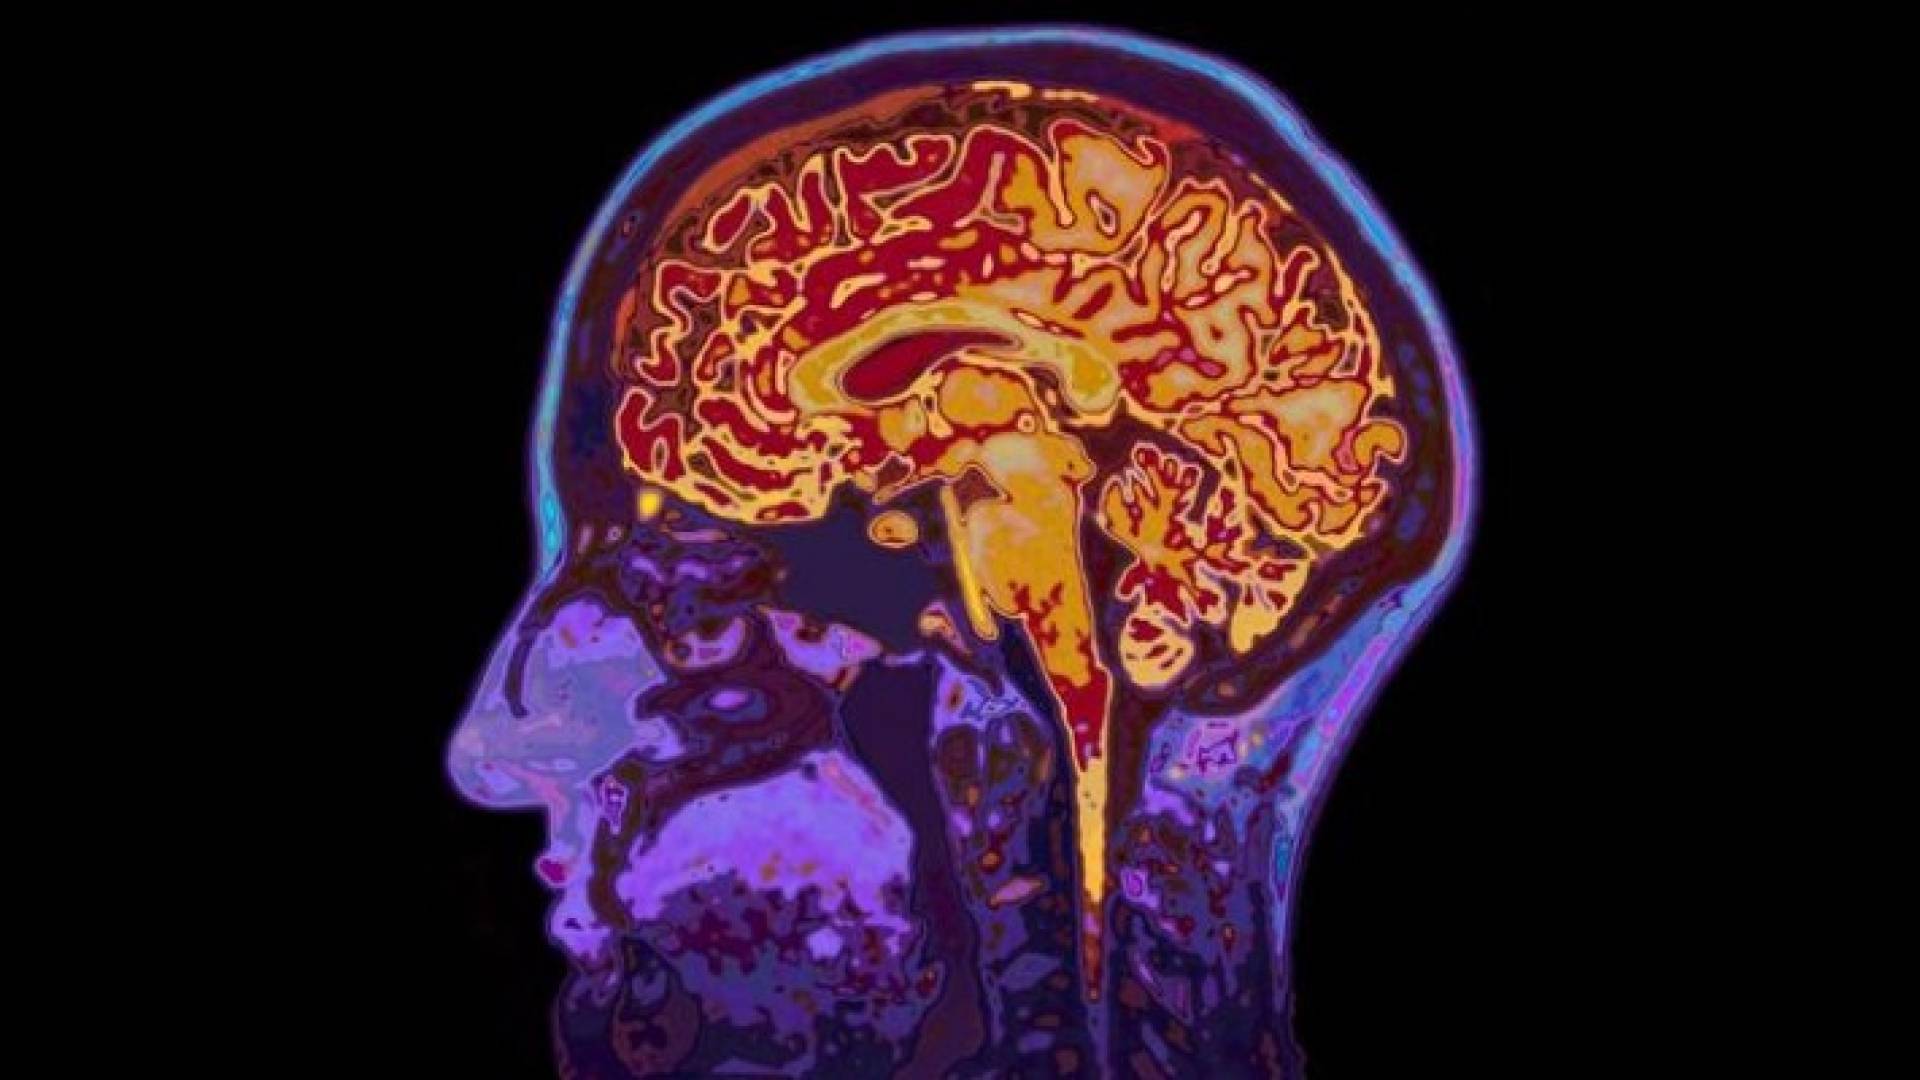

كيف تعمل عقولنا على تحليل اللغات؟

ومنذ أكثر من قرن تم التأكد من أن مقدرتنا القصوى على استيعاب اللغة تقع في الأغلب بالشق الأيسر من أدمغتنا، وبالتحديد في جزأين: منطقة بروكا (المرتبطة بإنتاج الكلام والنطق)، والثانية هي منطقة فيرنيك (المسؤولة عن الإدراك، وأي ضرر يمكن أن يلحق أيا من هذين الجزأين، سواء جراء إصابة أو سكتة، يمكنه أن يؤدي إلى مشاكل في اللغة أو الكلام أو " aphasia" المعروف باسم "الحبسة" وهي فقدان المقدرة على النطق باللغة.

خلال العقود الماضية اكتشف علماء الأعصاب بأن استيعاب اللغة والكلام وتحليلهما ليسا بالعملية البسيط، وأنهما لا يقتصران على جزأين فقط من الدماغ أو على شق واحد منه، وأن الدماغ يمكنه أن يكبر حجما كلما تعلمنا لغات جديدة.

إذ كشفت دراسات حديثة بأن الكلمات ترتبط بمناطق مختلفة من أدمغتنا وفقا لموضوع الحديث أو معناه، ويهدف علماء الأعصاب إلى إعداد أطلس ثلاثي الأبعاد للمواقع التي يتفاعل بها الدماغ مع الكلمات المختلفة، وذلك بإجراء مسح لأدمغة أشخاص خلال استماعهم لمحطة راديو لعدة ساعات.